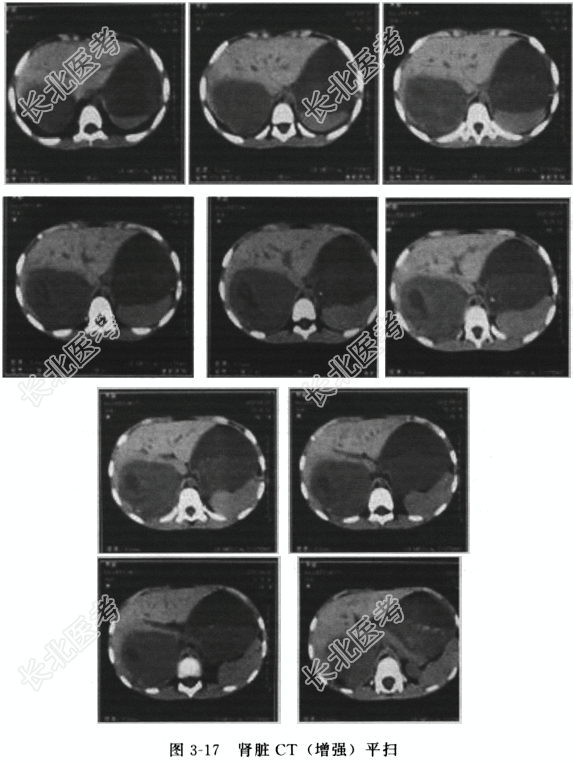

患者为男性儿童。入院时PS评分为1分,肾脏平扫(图3-17)示:右肾见一7.5cm×4.8cm×6.0cm占位,增强扫描后病灶局部明显强化,边界清楚,腹主动脉旁淋巴结肿大,下腔静脉未见癌栓形成,左肾未见异常。胸部CT扫描显示双肺未见异常。